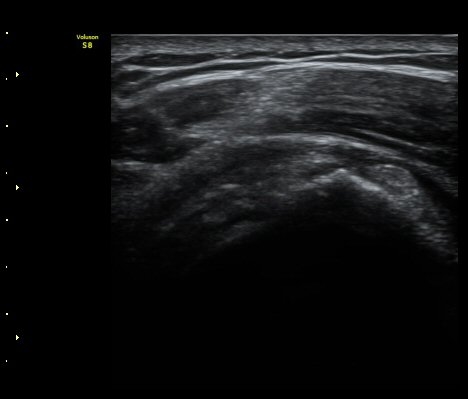

±Ø»ó°Ç Á¾´Ü¸é°Ë»ç¿¡¼­ Á¤¸Æ³¶³» ¼ö¾×Àú·ù¿Í ±Ø»ó°Ç³» ¼®È¸È­À½¿µÀÌ °üÂûµÈ´Ù(±×¸² 2, 3).

±Ø»ó°Ç ¸»´ÜºÎ Á¾´Ü¸é°Ë»ç¿¡¼­ ±Ø»ó°Ç°ú Á¡¾×³¶³» ¼®È¸È­°¡ °üÂûµÈ´Ù(±×¸² 4, 5).